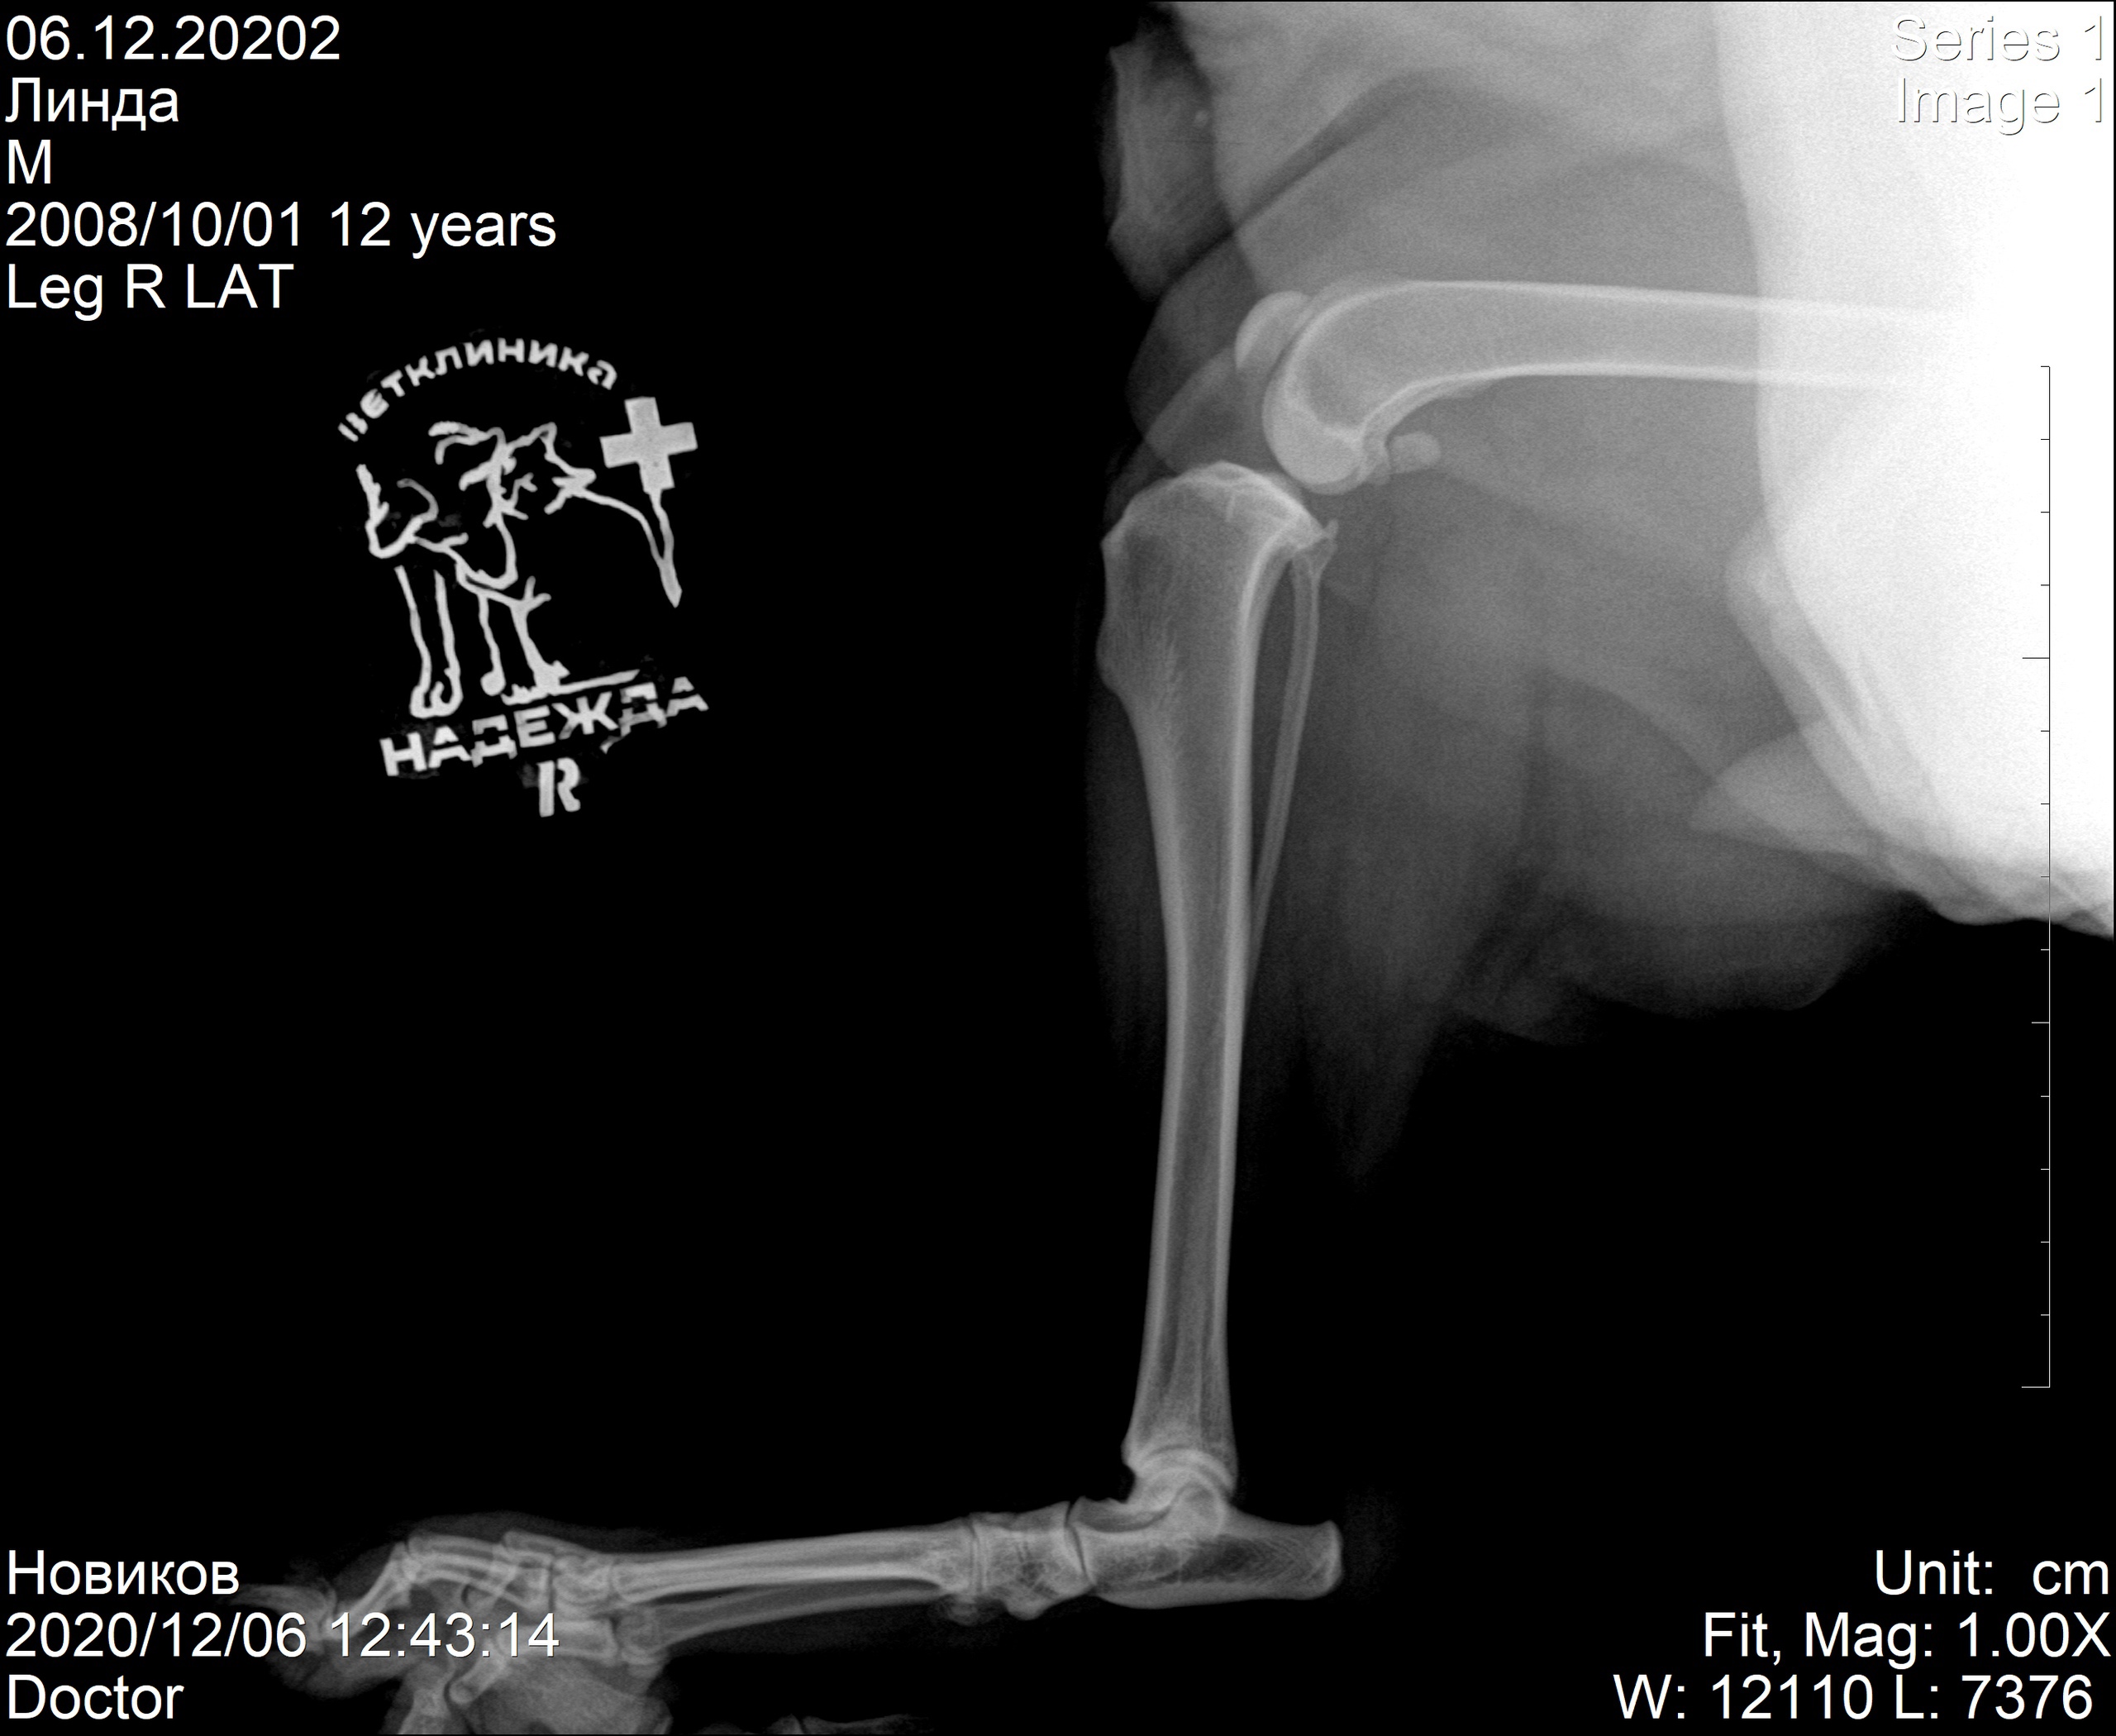

Наш пациент собака возрастом 13 лет по кличке линда. Обратились в нашу клинику с жалобами на хромоту на заднюю правую лапу. После проведенных исследований был поставлен диагноз - разрыв передней крестообразной связки правого коленного сустава.

Снимок 1 до операции.